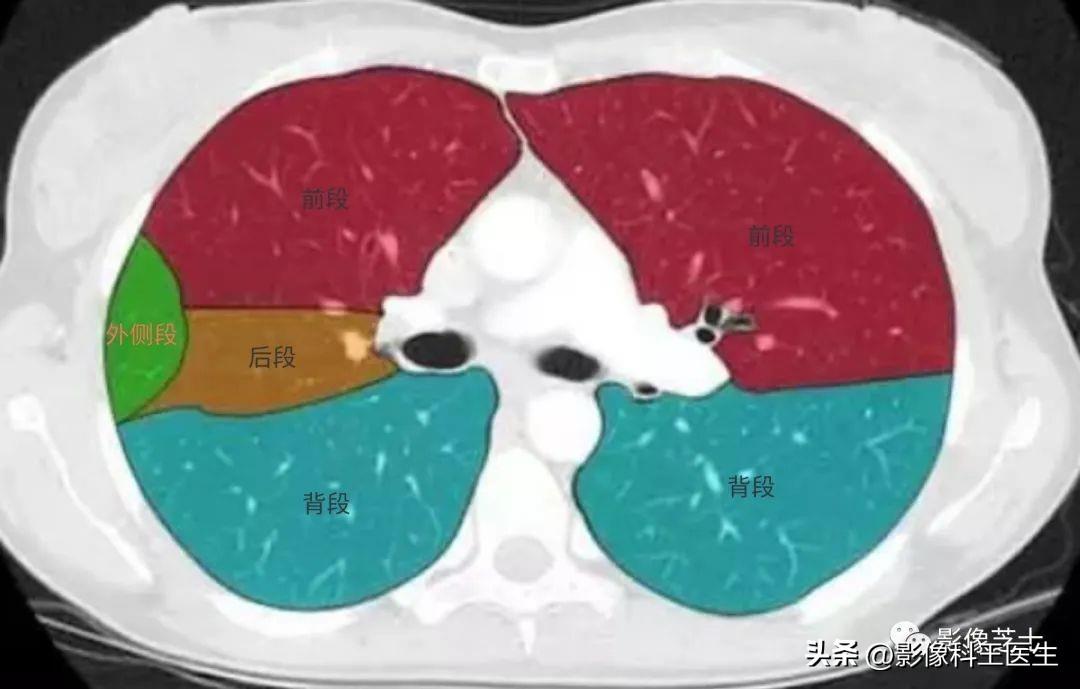

肺的分段